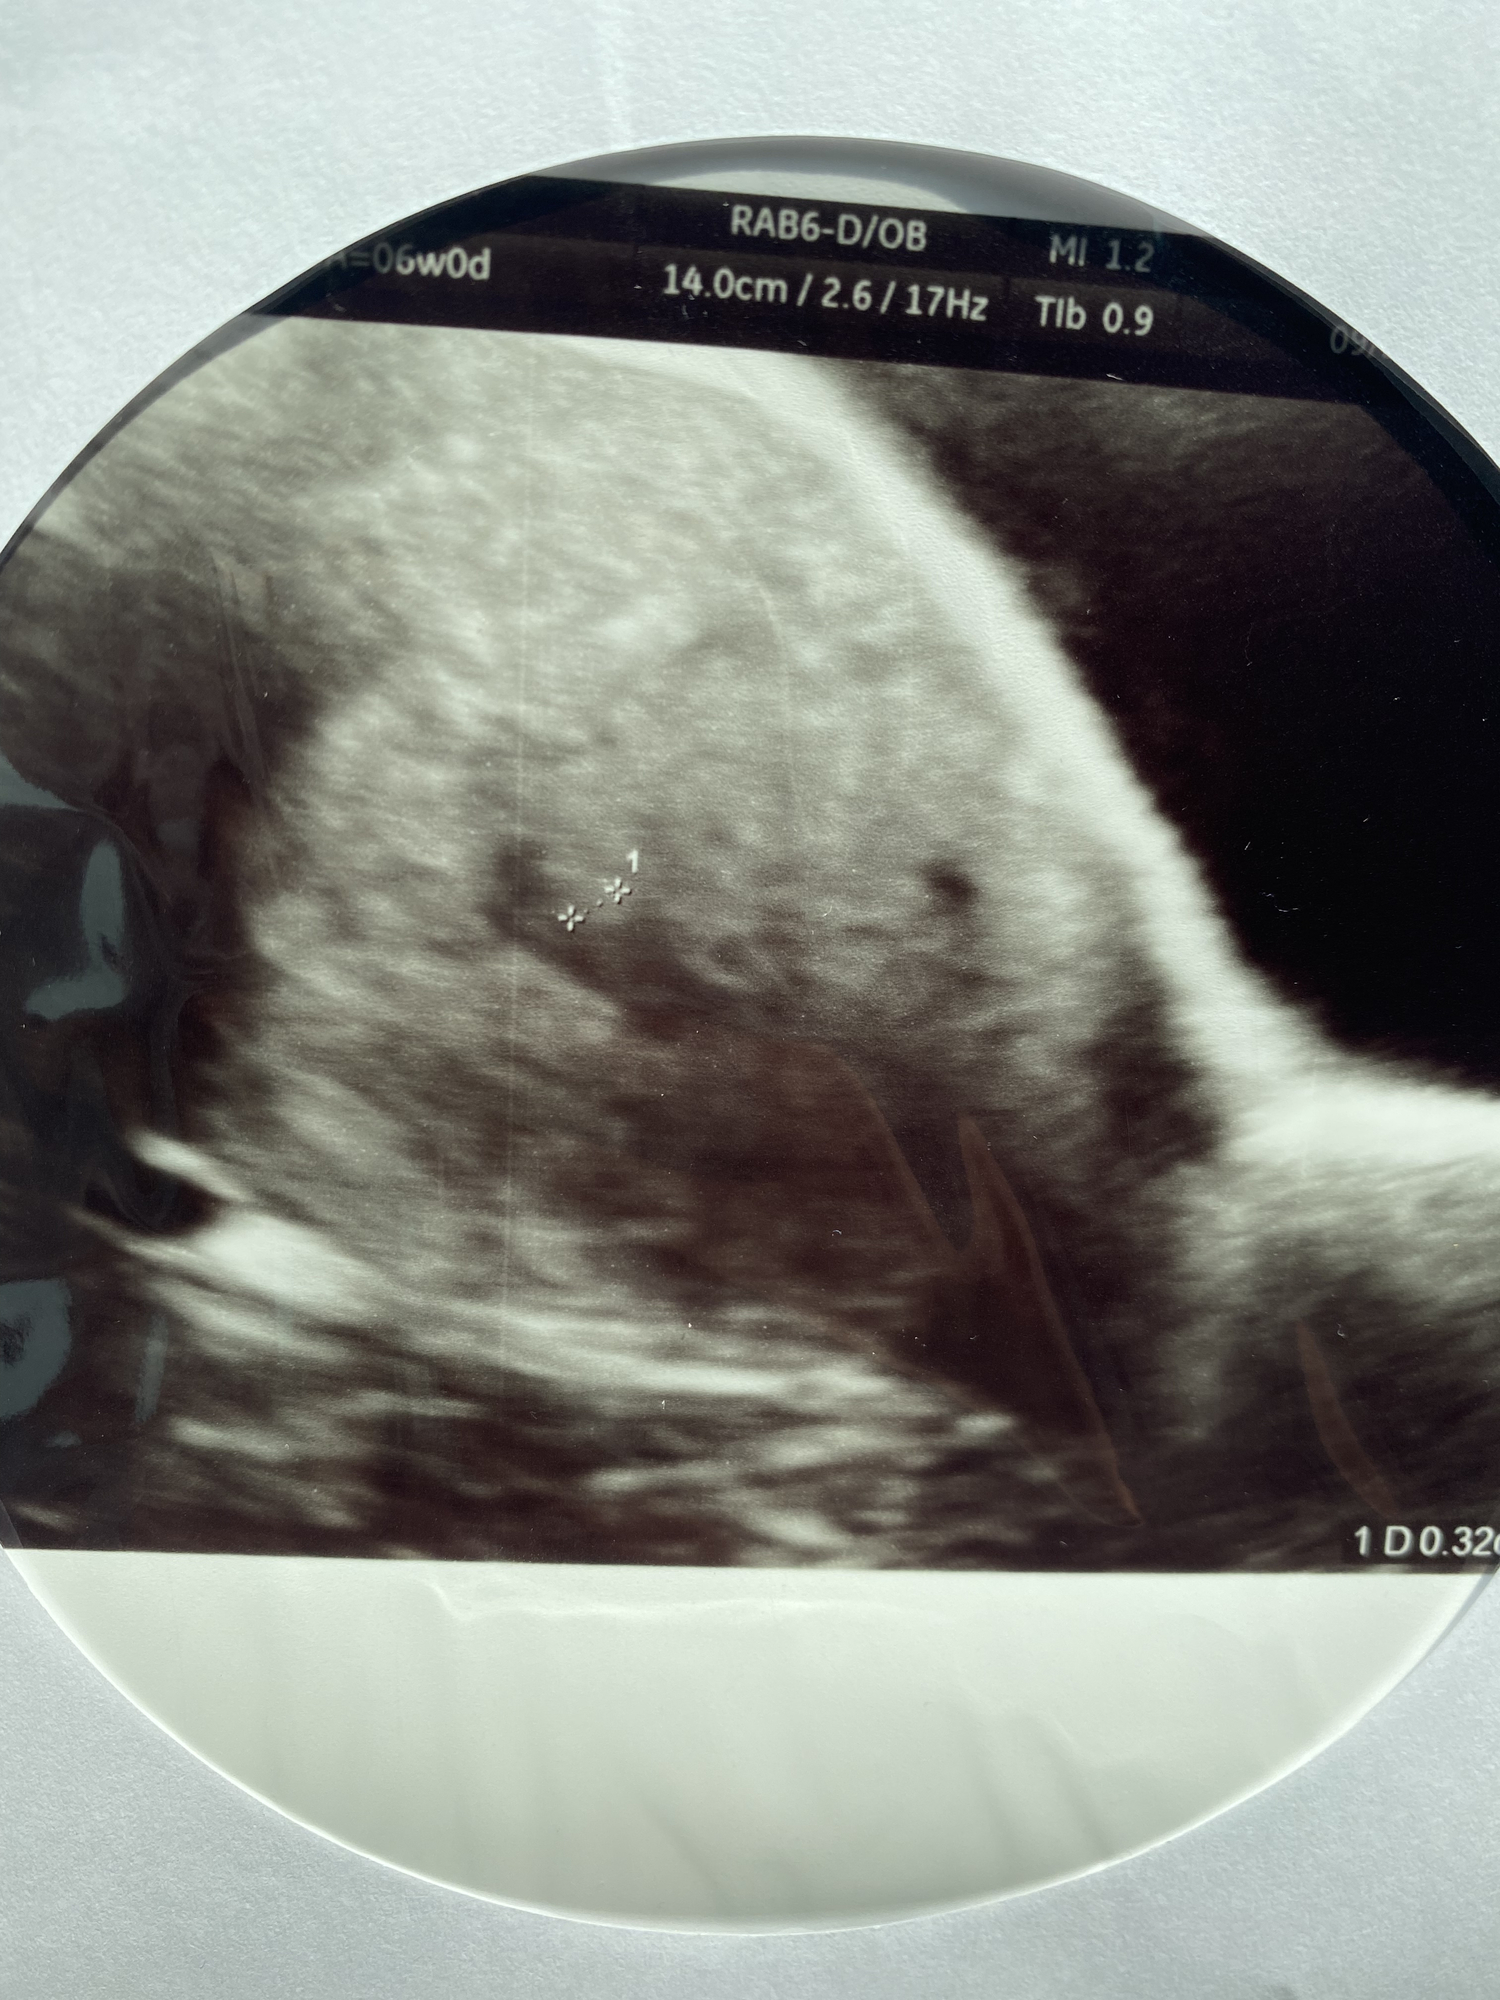

I went today to get a ultrasound in those private places and they didn’t see anything . I’m 6 weeks today can it be that is so early . Here’s the ultrasound they took they were able to see this only .

Only a real doctor and trained US tech will be able to tell you for sure. If you’re not 100% certain when you conceived you may have ovulated late. 6 weeks is still a little early to see much.

At six weeks your best bet to see anything would be with a transvaginal ultrasound, not the abdominal ultrasound you received. That place should have told you it was too early so I’m sorry you were taken advantage of. Your best next step is scheduling an appointment with your OB. Best of luck!